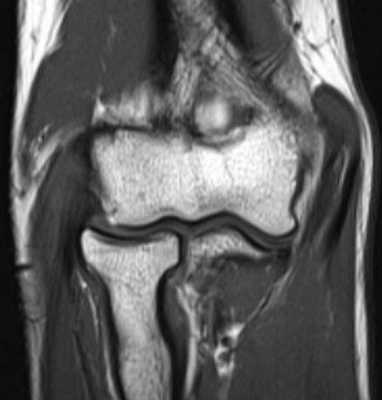

Локтевой сустав (МРТ анатомия)

Описание исследования 1 - головка лучевой кости 2 - венечный отросток локтевой кости 3 - локтевая кость 4 - локтевой отросток 5 - сухожилие трехглавой мышцы 6 - медиальная коллатеральная связка локтевого сустава 7 - лучевая коллатеральная связка локтевого сустава 8 - латеральная коллатеральная связка 9 - латеральный надмыщелок плечевой кости 10 - сухожилие двуглавой мышцы плеча 11 - плечевая мышца 12 - длинный лучевой разгибатель запястья 13 - блок плечевой кости 14 - локтевая мышца 15 - глубокий сгибатель пальцев 16 - локтевой сгибатель запястья 17 - трехглавая мышца 18 - кольцевидная связка лучевой кости 19 - двуглавая мышца плеча 20 - супинатор 21 - плечелучевая мышца 22 - круглый пронатор 23 - разгибатель пальцев 24 - лучевой сгибатель запястья 25 - поверхностный сгибатель пальцев 26 - локтевой нерв 27 - локтевой сгибатель запястья 28 - короткий лучевой разгибатель запястья 29 - общее сухожилие разгибателей 30 - общее сухожилие сгибателей и круглого пронатора 31 - бугристость лучевой кости 32 - головка плечевой кости 33 - медиальный надмыщелок плечевой кости 34 - гребень супинатора 35 - трапециевидная связка (lacertus fibrosus) 36 - наружная головка трехглавой мышцы плеча 37 - длинная головка трехглавой мышцы плеча 38 - медиальная головка трехглавой мышцы плеча 39 - общее сухожилие сгибателей